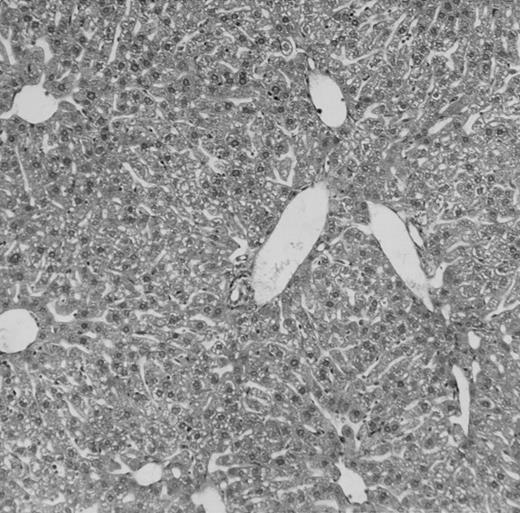

Histologic findings. Organs were collected at different times after BMT and tissue sections were stained with hematoxylin and eosin. Original magnifications for spleen (left) and liver (right) are ×40 and ×100, respectively. (A) B6 mice receiving FVB BM plus EpTK T cells. (B) Control group receiving BM only.

(C) B6 mice receiving FVB BM plus EpΔTK T cells and treated with GCV. (D) B6 mice receiving FVB BM plus EpΔTK T cells, treated with GCV, and developing a late onset GVHD (day 54).

FVB BM-grafted B6 mice: a model of lethal GVHD.We developed a model of GVHD resulting in 100% mortality soon after BMT using FVB mice, a strain not previously used as BM donors in experimental allogeneic BMT. We tested different combinations of recipient irradiation doses, as well as injected BM cell and CD3+ peripheral T-cell numbers. When 10-Gy–irradiated B6 mice were reconstituted with 107 FVB BM cells, we observed prolonged survival, whereas all ungrafted animals died before day 16 (Fig 2). In these conditions, more than 98% of splenocytes were of donor origin (Fig 3A). When 107 CD3+ peripheral T cells from mice of FVB genetic background were added to the FVB BMT, all animals died of GVHD between days 7 and 34 (Fig 2). Similar results were obtained using either PBS-treated mice receiving EpTK or EpΔTK peripheral T cells or GCV-treated mice receiving FVB nontransgenic peripheral T cells. Notably, this observation also indicates that both TK- and ΔTK-expressing T cells in the absence of GCV are fully competent to induce a lethal GVHD. Histopathologic examination of spleen and liver of these animals showed characteristic GVHD lesions such as (1) architecture disruption, necrosis, and congestion in the spleen; (2) hepatic periportal necrosis; (3) mononuclear portal infiltrates; and (4) endothelialitis of portal or centrolobular veinules (Fig 4A). By comparison, B6 mice receiving only FVB BM had a normal histology (Fig 4B).

Using this delivery mode, we observed that mice receiving a 7-day GCV treatment initiated at the time of transplantation were protected from GVHD. At day 60, the survival rate was 100% in the GCV-treated group receiving EpTK CD3+ T cells, and was still 92% at the end of a 120 day follow-up (Fig 2A). Protected mice were apparently healthy, presented no visible skin lesions, and gained weight comparably to controls receiving only BM (data not shown). Hematologic reconstitution was analyzed by flow cytometry at different times from day 14 to day 212. Splenocytes of GCV-treated animals were of donor H-2q origin in the B-cell (B220+) and non–B-cell (B220−) compartments, the latter containing donor Thy1.1+ T cells but no recipient Thy1.2+ T cells (Fig 3B). Finally, histological analysis in these animals showed nodular architecture in the spleen and no significant hepatocyte necrosis or portal mononuclear cell infiltrates in the liver (not shown) and similar to control animals receiving only BM. Taken together, these data indicate that a GCV treatment, administered at the onset of allogeneic BMT and with a course as short as 7 days, abrogates GVHD and allows a full recovery from the lethal irradiation.